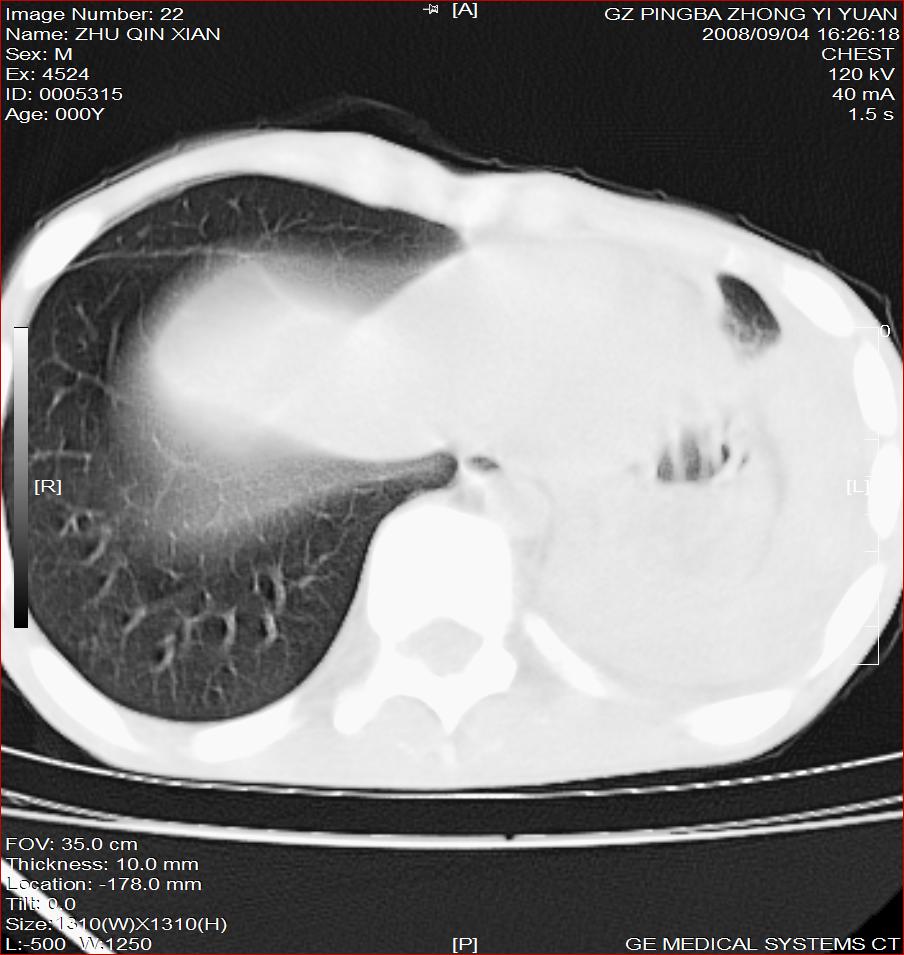

以下是引用随光逐影在2008-9-4 20:05:00的发言:[br]1)考虑两肺结核。2)左侧胸膜炎(胸膜肥厚、粘连,胸腔积液)。3)左侧局限性气胸。

以下是引用子十在2008-9-4 19:34:00的发言:[br]左上肺结核并空洞及双肺播散。节段性肺不张、胸腔积液、胸膜肥厚粘连。[br]